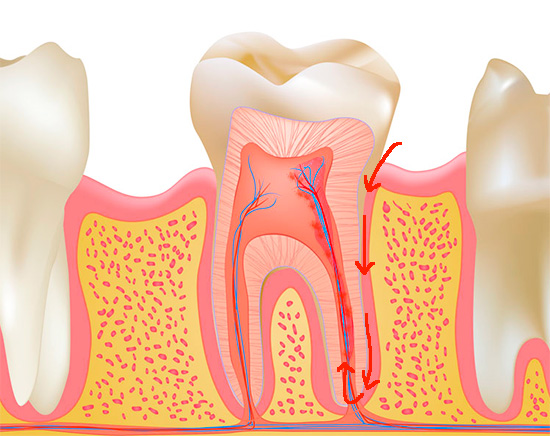

L'immagine seguente mostra schematicamente il classico sviluppo della pulpite - dopo carie profonde:

La causa più comune (eziologia) della pulpite è carie profonde. Nel processo di approfondimento della cavità cariata, si verifica la penetrazione diretta o indiretta dei microbi nel tessuto pulpare. Con accesso diretto, l'infezione va direttamente alla polpa aperta e con accesso indiretto, attraverso i tubuli dentinali che penetrano nello spessore della dentina.

- attraverso una corona dentale (complicazione della carie)

- attraverso l'apertura dell'apice della radice con la manifestazione di pulpite retrograda.